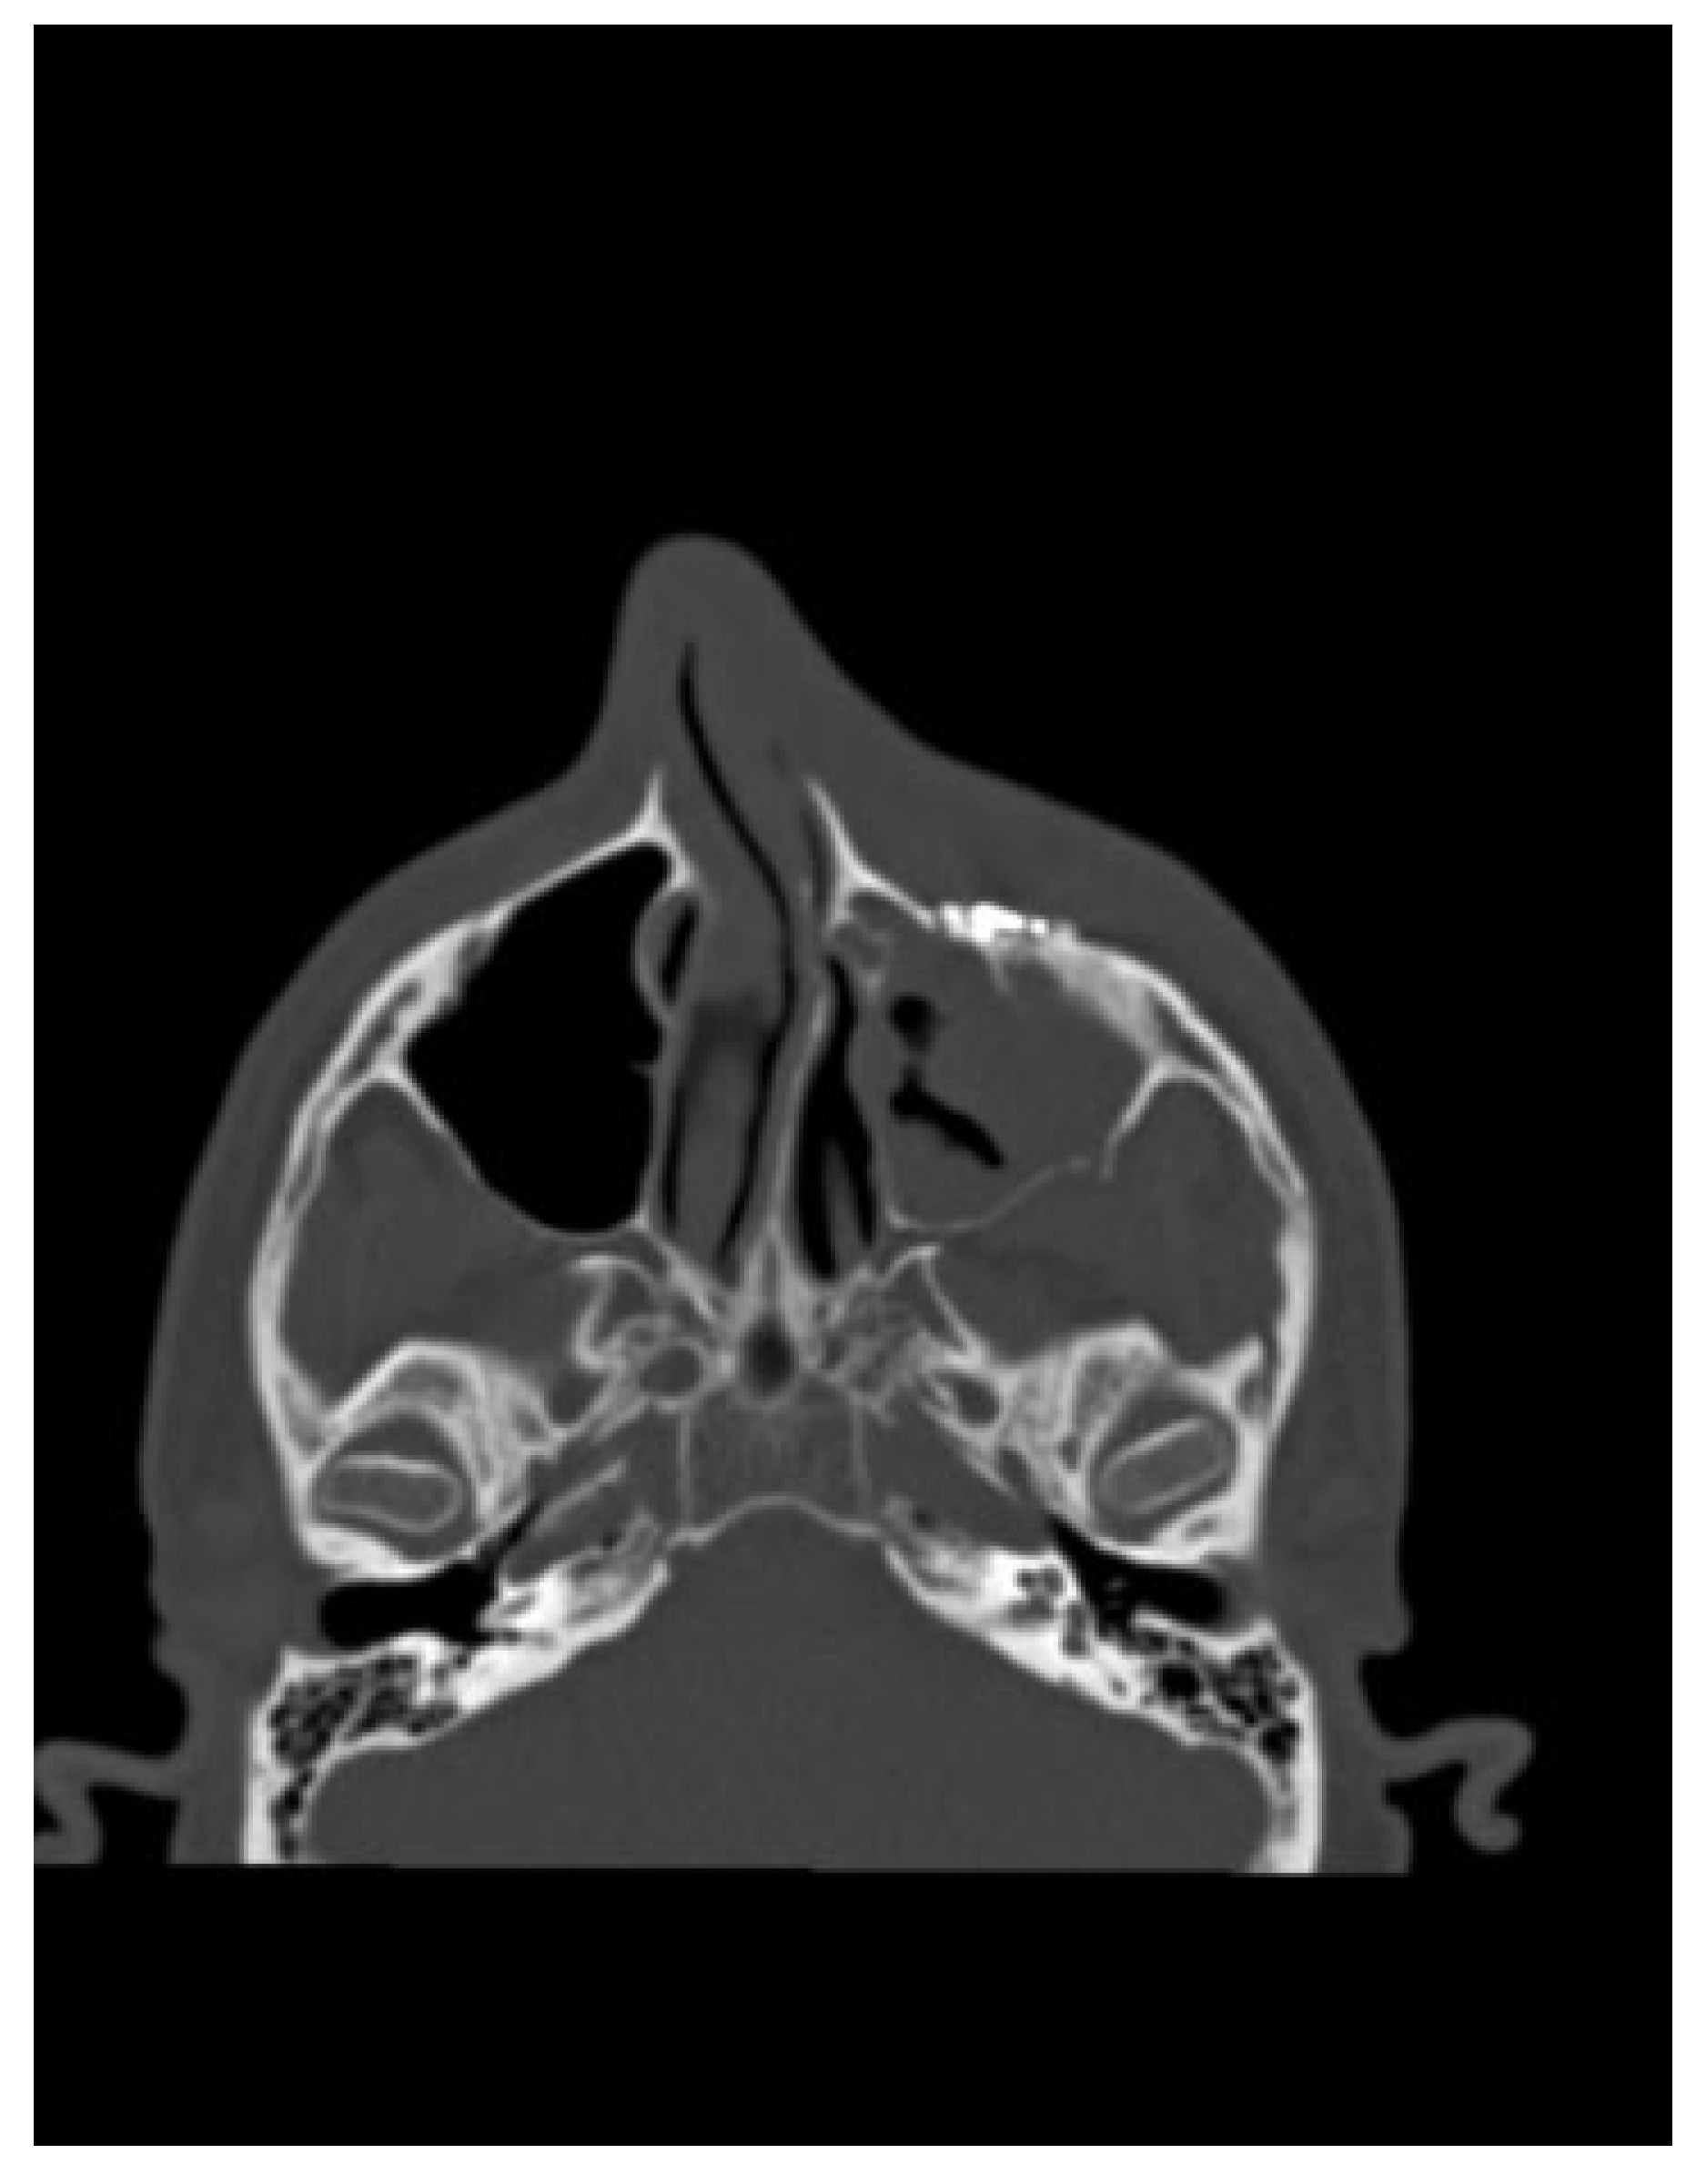

The first complication involved a 32-year-old man injured due to an alleged assault, resulting in a severe left orbitozygomatic fracture. The patient had paraesthesia to the distribution of the left infraorbital nerve (Figure 4).

Figure 4. Axial CT shows the defect in the left infraorbital region.